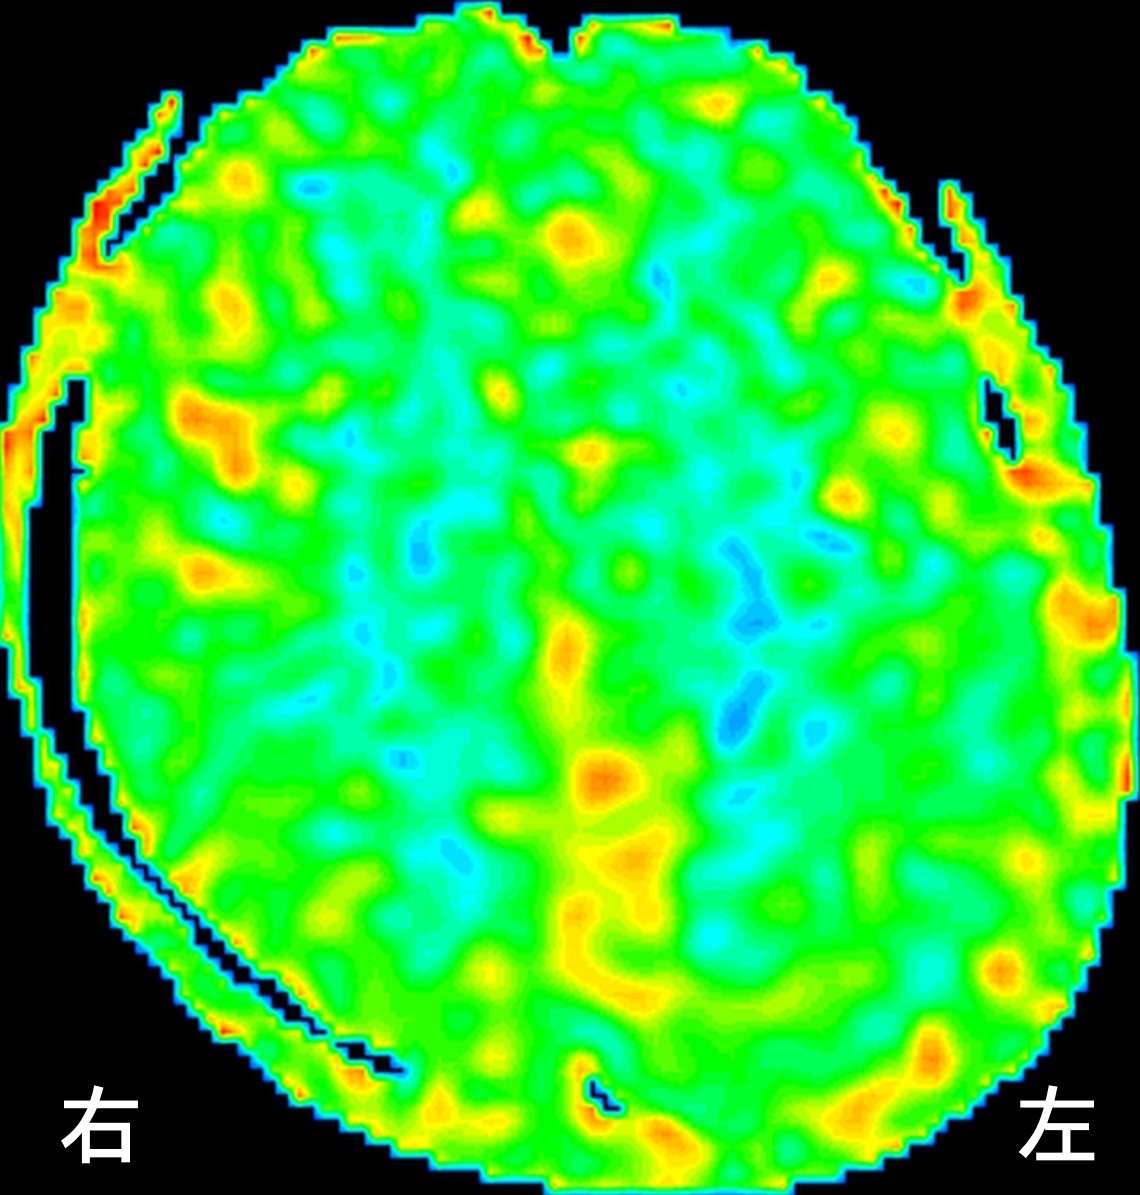

ASL(arterial spin labeling)法という、MRIで脳血流を評価する検査を行ったところ、

もやもや病と片頭痛

右の前頭葉、側頭葉、後頭葉で血流が低下しています。(青い場所が血流の悪い部分です)さらに、時間経過を追って血流の変化を見てみると、